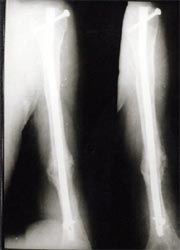

病例四、

肱骨骨不连的骨断端多有硬化而骨干骨质疏松、遗留有以往手术的钢板、

钉孔,骨吸收骨干变细有严重骨缺损,治疗困难较大。

带锁髓内钉内固定,解决骨质疏松、骨干变细和骨缺损等情况

下的固定问题,进行复合骨髓细胞的植骨,促进骨折愈合